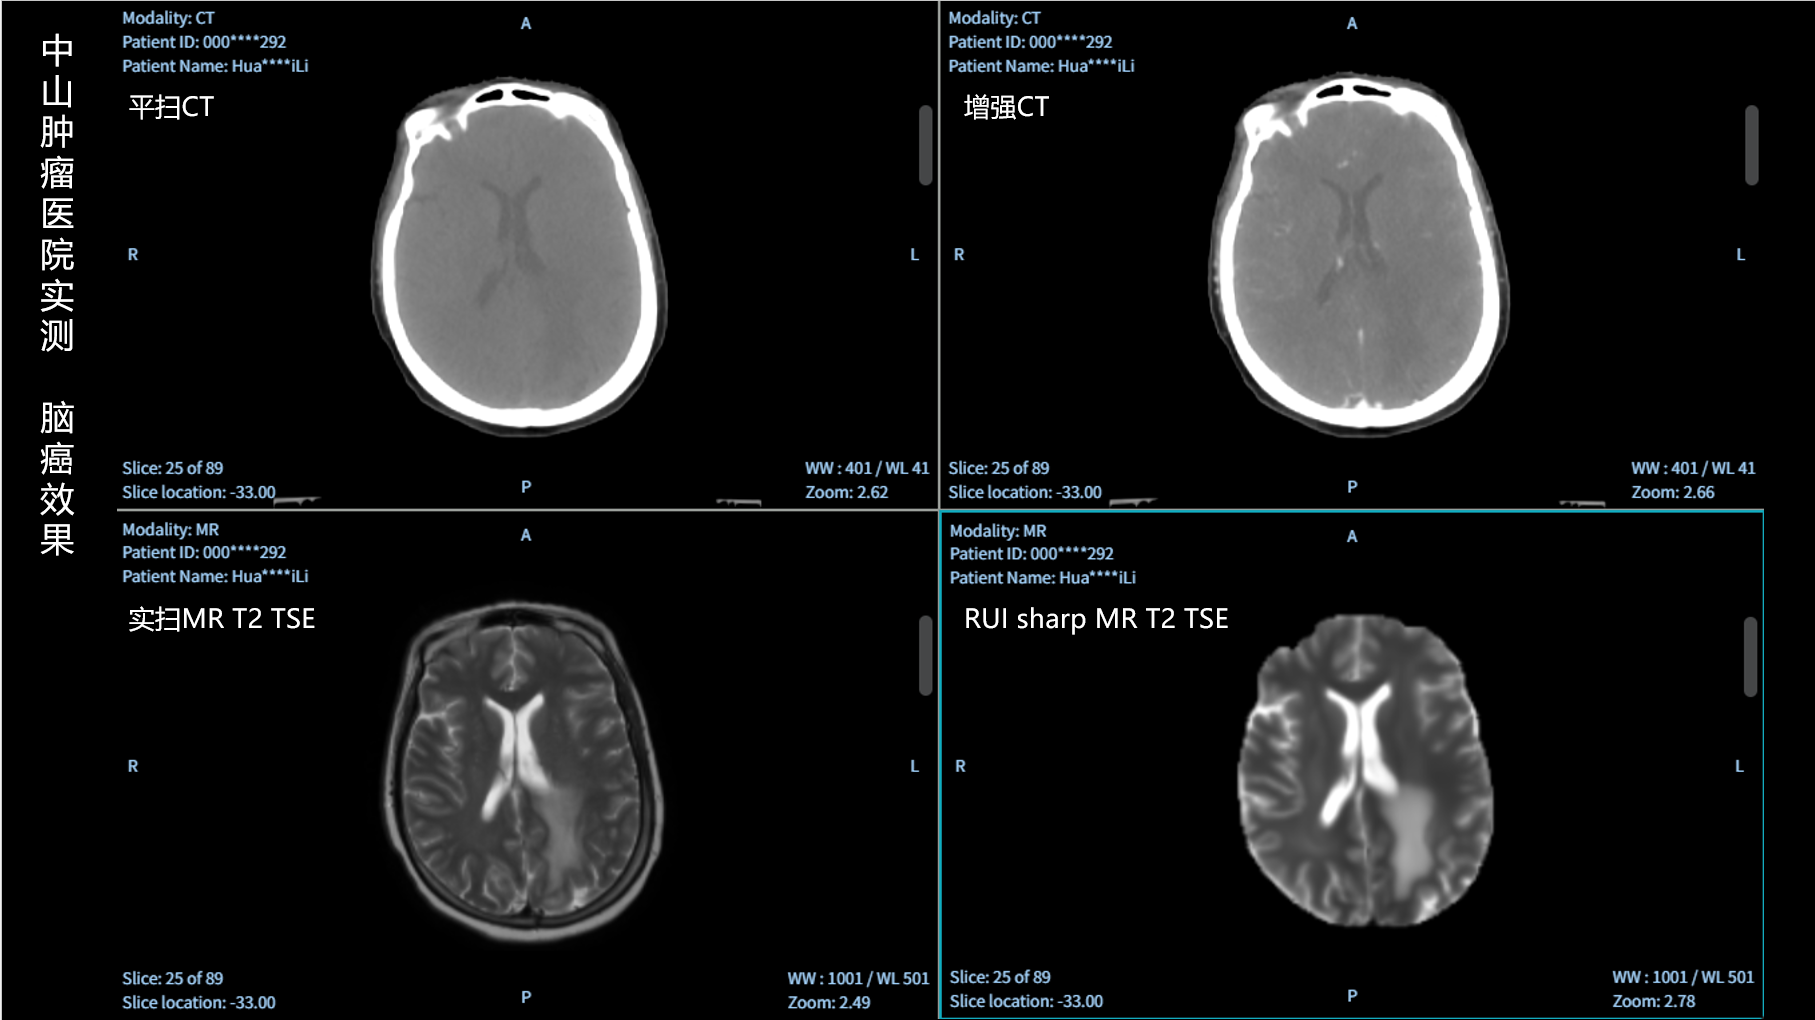

RUI sharp H(锐影)可在不依赖MRI的前提下,显著提升头部CT图像的软组织分辨率,为临床提供更高质量的辅助信息,尤其适用于MRI资源受限或较难配准的头颈部放疗感兴趣区勾画场景。

可大幅提高头部CT影像软组织分辨率,使肿瘤和周边器官显示更清晰,为放疗靶区勾画提供参考。

无需图像配准,CT和锐影图像同源,可匹配、叠加、"淡入淡出"显示。